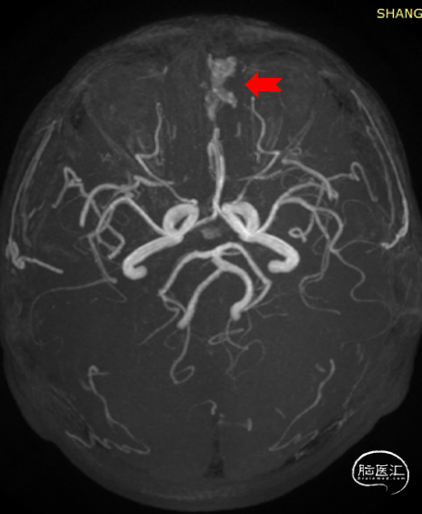

➢术前影像学检查:CTA及MRA提示左侧前颅底硬脑膜动静脉瘘(DAVF)。

术前根据头颅CTA及MRA检查,考虑前颅底硬脑膜动静脉瘘,经DSA进一步确诊。

造影提示左侧前颅底眼动脉末端分支供血的DAVF经矢状窦起始段回流,回流静脉迂曲,局部可见粗大的静脉球。